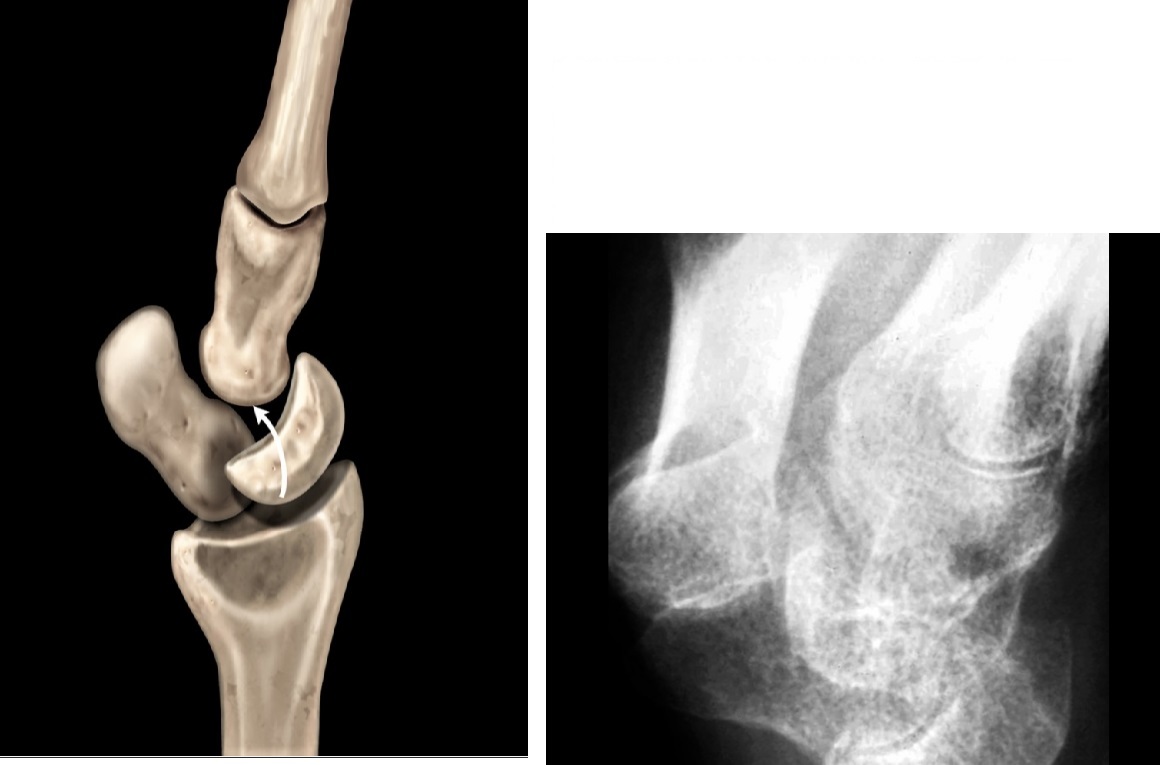

capitate is dislocated dorsal and nudges the lunate volarly but it is not fully dislocated

Ligament = Triquetrolunate interosseous ligament

Associated with Triquetral fracture

Lunate dislocated volar direction

Ligament damaged = Dorsal radio lunate ligament